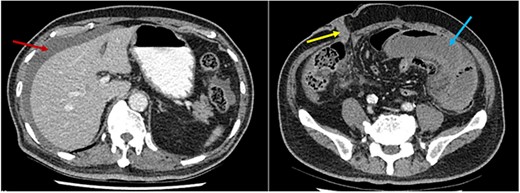

Series of axial images of initial CT progressing from most superior (image A) to inferior (image D). The EIA has been highlighted in yellow from immediately inferior to the bifurcation of the common iliac artery. The internal iliac artery can be seen in red in image A. Images B and C demonstrate a collapsed EIA between dilated loops of small bowel suggesting involvement in the internal hernia. Image D demonstrates opacification of the EIA indicating flow distal to the internal hernia. Dilated loops of bowel have been marked with a blue star.

Pre-operative identification of internal hernias would allow for optimal management and planning, however diagnosis of intestinal herniation causing SBO on imaging can be challenging. CT features such as atypical bowel configuration, mesenteric abnormalities (including displacement, twisting or stretching of mesenteric vessels) and the position of surrounding viscera raise the index of suspicion of internal herniation [13]. In this case, retrospective review of the CT scan demonstrates the proximity and compression or partial occlusion of the segment of EIA within the closed-loop obstruction (Figs 3 and 4). This is concordant with our intra-operative findings of a narrow, non-pulsatile structure.